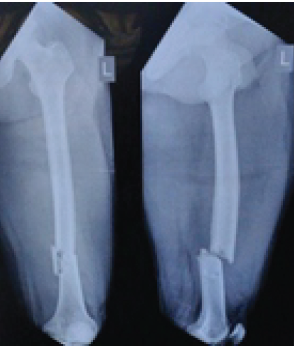

Figure 1: Pre-operative anteroposterior and lateral views showing a distal third fracture of femur.

Out of all study participants, 58 patients had closed fractures and rest 2 patients had compound fractures. The mean operation-injury interval was 5.5 ± 0.67 days for antegrade nailing and 5.8 ± 0.65 days for retrograde nailing. The mean duration of the surgery was 85 ± 2.15 min for retrograde nailing and 95 ± 1.39 min for antegrade nailing. Mean time for radiological union with retrograde nailing was 10 ± 0.38 weeks (Fig. 1, 2, 3, 4) and with antegrade nailing, it was 14 0.44 weeks (Fig. 5, 6).